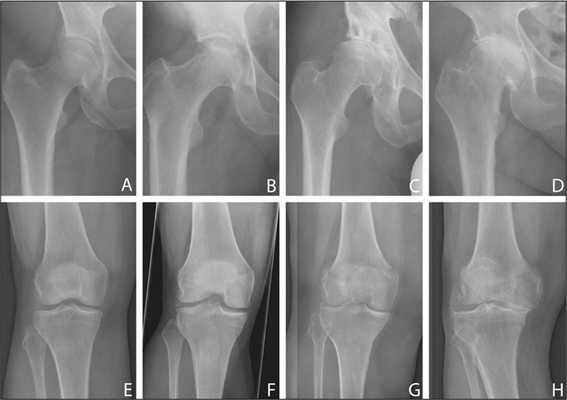

Шеечно-диафизарный угол (угол инклинации шейки бедра)

Шеечно-диафизарный угол (угол инклинации шейки бедра) - угол между шейкой и диафизом.

- у взрослых: 125° - 135°.

- у детей:

- новорожденные: 134°

- 1 год: 148°

- 3 года: 145°

- 5 лет: 142°

- 9 лет: 138°

- в подростковом возрасте - 130°

Измеряется между линией соединяющей центр головки бедренной кости и центр шейки бедренной кости и линией проведенной через середину диафиза.

Варусная деформация шейки (соха vara) - это состояние, при котором шеечно-диафизарный угол меньше среднего угла, соответствующего возрасту. Может быть врождённым и приобретённым.

Вальгусная деформация (соха valga) - это состояние, при котором шеечно-диафизарный угол больше среднего угла, соответствующего возрасту. Может быть врождённым и приобретённым.